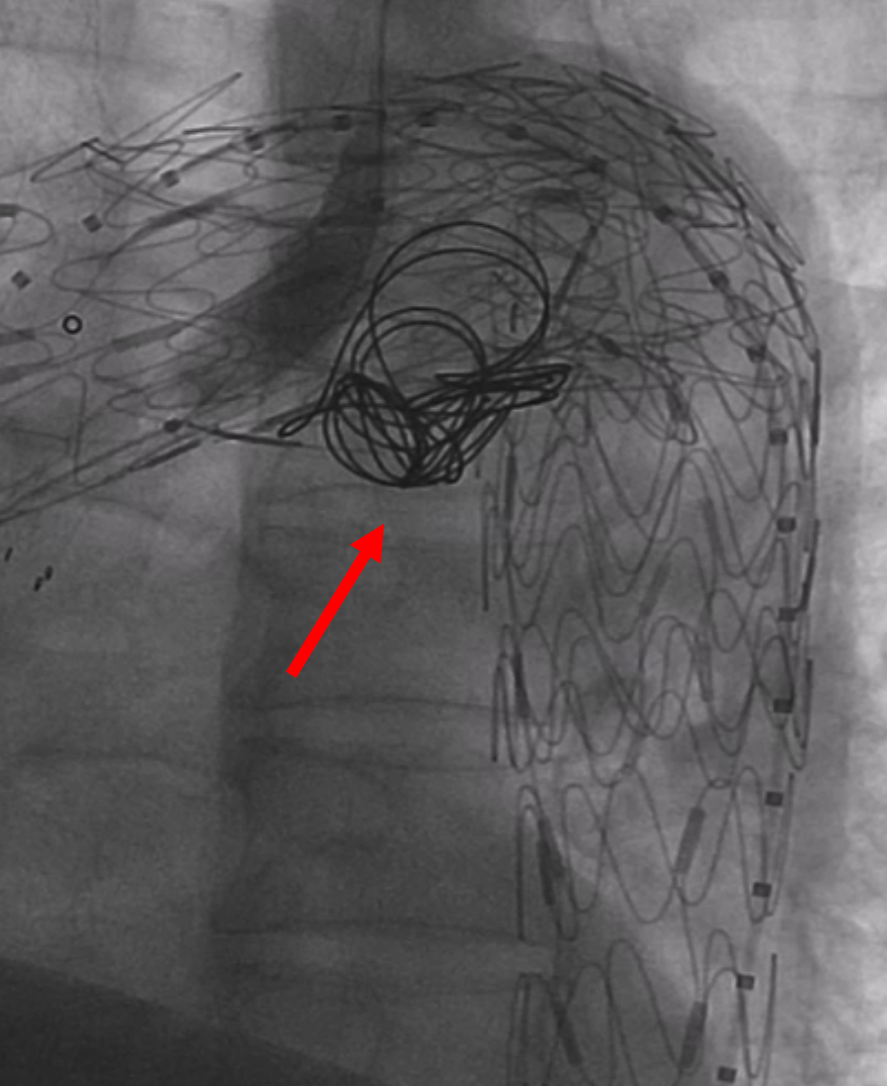

【病例2】主动脉B型夹层,

2016年外院TEVAR术后II型内漏

术后8年随访发现假腔明显扩大,最大直径达96mm,伴胸背疼痛,有手术干预指征。

再干预方案:弹簧圈栓塞分支血管(LSA栓塞),覆膜支架+封堵器+弹簧圈覆盖左肾动脉破口。

修复结果:进入假腔血流明显减少,胸背疼痛症状明显缓解。

LSA弹簧圈栓塞